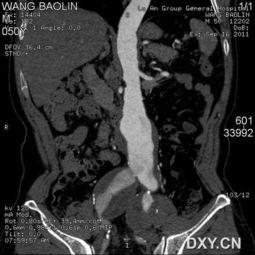

主动脉,是人体内最大的动脉,负责将心脏泵出的血液输送到全身各个部位。而主动脉支架,就是用来修复主动脉病变的一种医疗器械。当主动脉发生病变,如主动脉瘤、主动脉夹层等,就可能引发生命危险。这时,主动脉支架就派上用场了。

主动脉瘤是指主动脉局部扩张,形成囊状或梭状瘤体。国产主动脉支架可以有效地修复主动脉瘤,降低破裂风险。

2. 主动脉夹层

主动脉夹层是指主动脉内膜和中膜分离,形成夹层血肿。国产主动脉支架可以迅速封闭夹层,防止病情恶化。